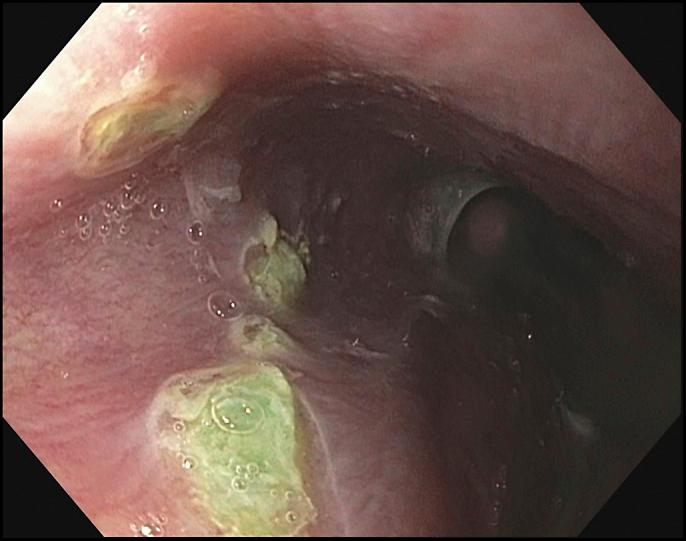

Although hepatic involvement in light chain-associated amyloidosis is common, clinical manifestations of hepatic amyloidosis are rare. In most cases, hepatomegaly serves as a clue to diagnosis. We report a unique case of a 48-year-old man from China with jaundice and noncirrhotic portal hypertension, with rapidly progressive liver failure, in the absence of hepatomegaly, secondary to systemic light chain-associated amyloidosis associated with multiple myeloma.

尽管轻链相关性淀粉样变性累及肝脏很常见,但肝淀粉样变性的临床表现却很少见。在大多数情况下,肝肿大是诊断的线索。我们报告了一例独特的病例,一名来自中国的48岁男性,患有黄疸和非肝硬化性门静脉高压症,继发于与多发性骨髓瘤相关的系统性轻链相关性淀粉样变性,在没有肝肿大的情况下出现快速进展的肝功能衰竭。